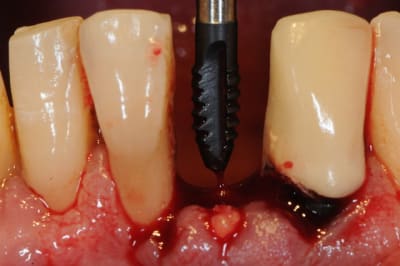

1)2)3) suite à de vilaines bactéries mangeuses d'apex (pas alapex, hein! lui il est immangeable) 31 est extraite 15 jours avant implantation.

1-2) incision

3) décollement

4)5) forêt pointeur (un petit coup de boule pour les kystes éventuelles et tissus mous)5

6) autre forêt pointeur (ici peu utile car l'extraction était récente)

7)contrôle de l'axe

8) radio (faut dire que le couloir dans lequel on peut mettre l'implant est étroit)